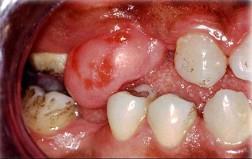

问题 组图为口内纤维瘤的外观,关于此病的描述不正确的是 ( )

选项 A.生长一般较缓慢 B.手术后不易复发 C.主要由纤维组织构成 D.有可能恶变 E.肿瘤边界清楚

答案 B